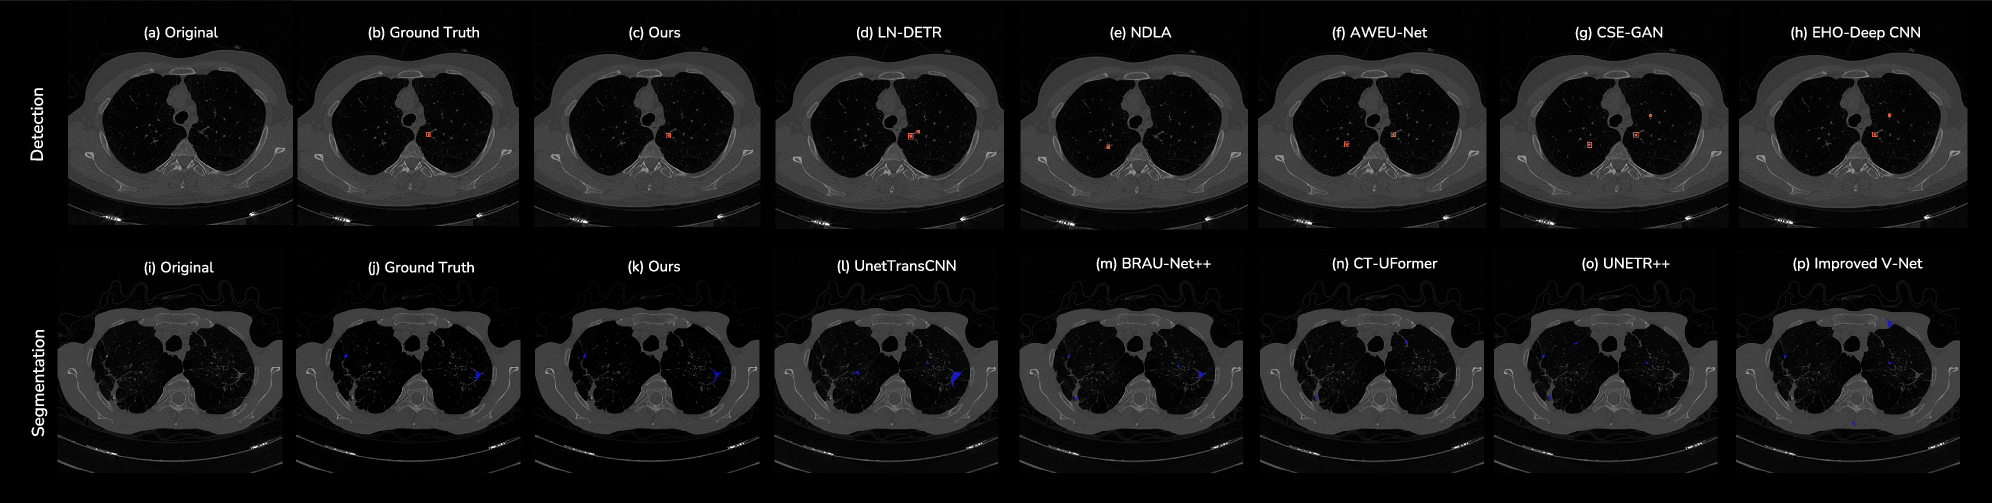

Fig. 1: Qualitative comparison of segmentation (top) and detection (bottom).

For each case, we show the original image, ground truth, ours, and a series of baselines arranged left-to-right in progressively worse visual quality relative to (c)(k)ours. Detection baselines: (d)LN-DETR, (e)NDLA, (f)AWEU-Net, (g)CSE-GAN, (h)EHO-Deep CNN, segmentation baselines: (l)UnetTransCNN, (m)BRAU-Net++, (n)CT-UFormer, (o)UNETR++, (p)Improved V-Net; Our method yields sharper boundaries and fewer false positives/negatives, with competing methods exhibiting increasing boundary erosion, missed lesions, and spurious responses to the right.